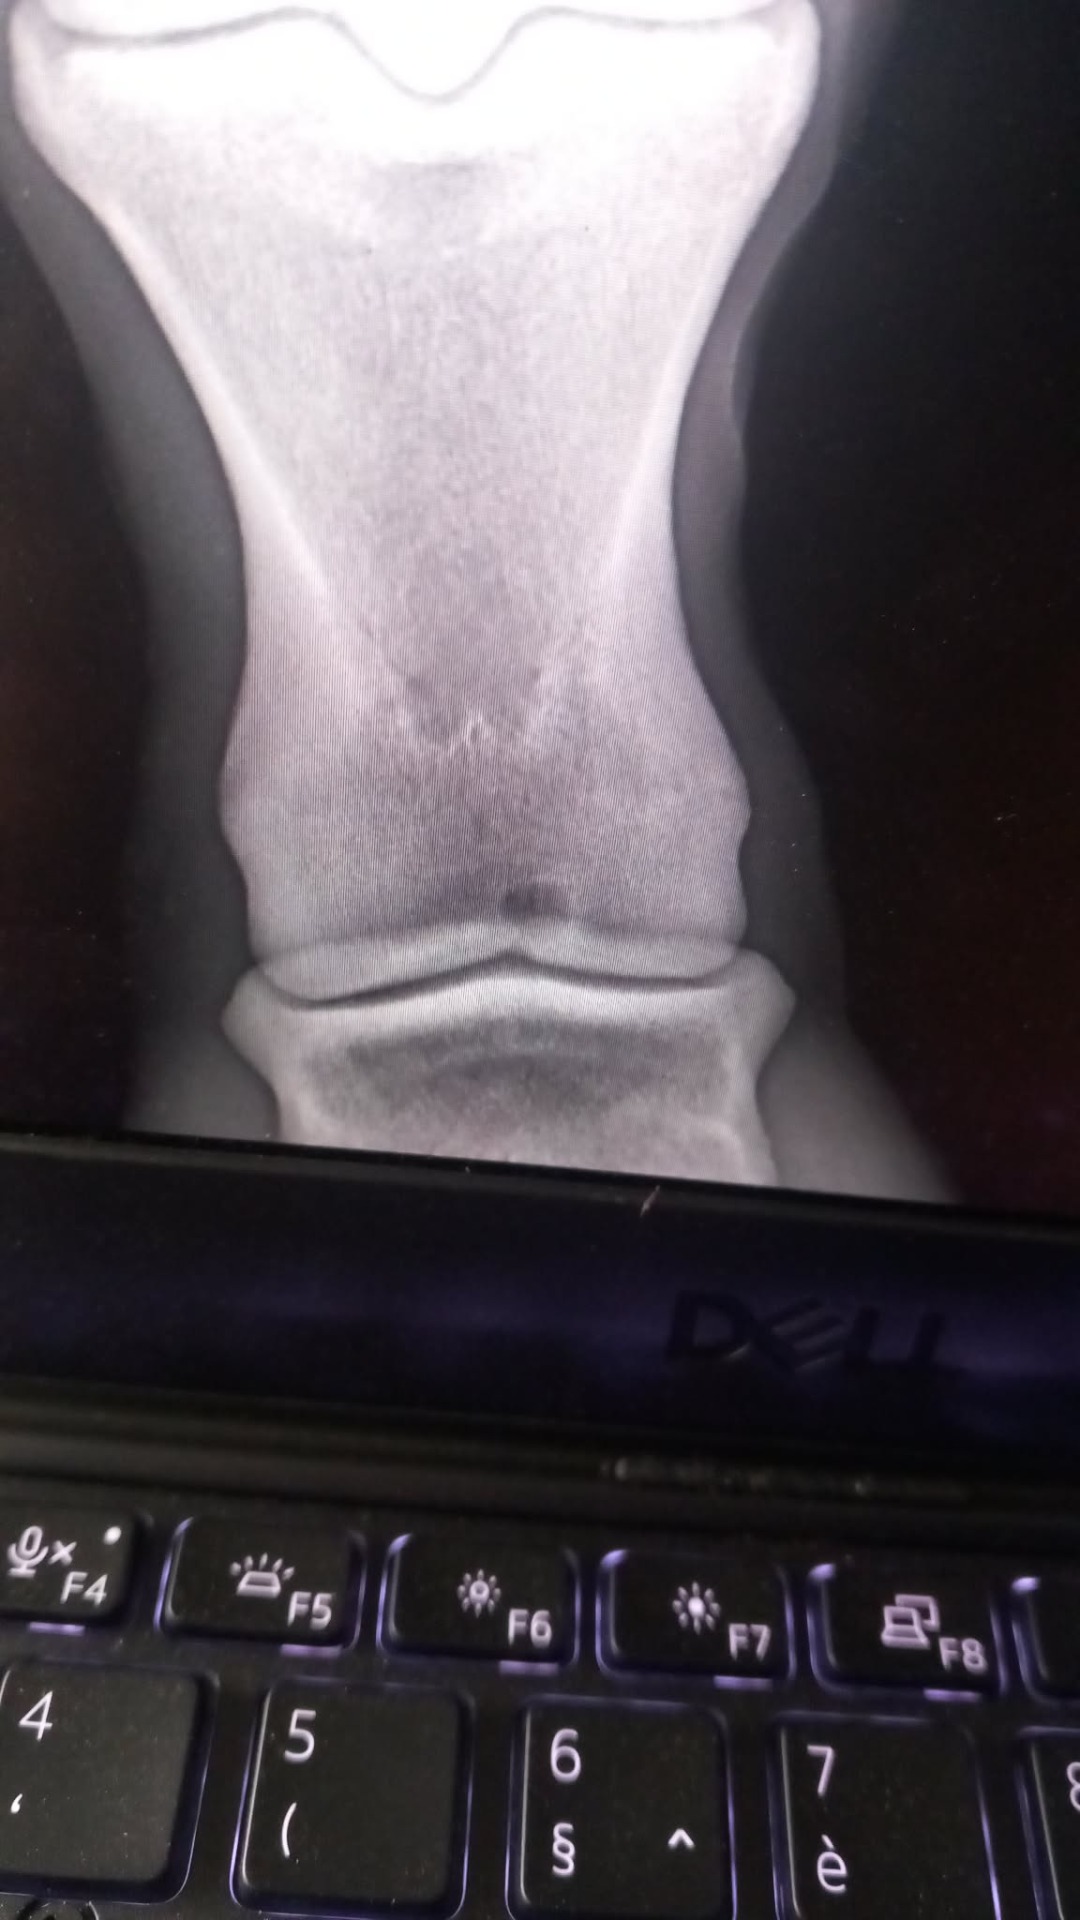

Radiografie

Wij bezitten de modernste uitrusting inzake radiografie. Dit kan gebruikt worden bij bijvoorbeeld mankheid en tandproblemen. Ons systeem kan volledig werken zonder stroom. Zo zijn we flexibel qua locatie.